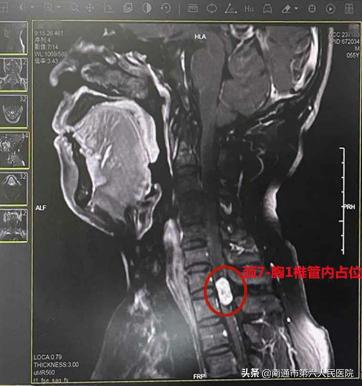

近日,冯先生夜间睡觉感觉肩膀发硬,双腿无力且酥麻感较之前更严重,这才来到南通六院(上大附院)就诊。核磁共振检查结果显示,原先体积较小的肿瘤已长成约1.2*0.6*0.6cm大小了。医生表示,如果任由它继续增长,将椎管内堵死,压迫神经,可能会致高位截瘫,后果不堪设想,冯先生这才下定决心切除肿瘤。

手术需要在不损伤脊髓的前提下完整切除肿瘤,术中还要控制减少出血,这是医生们术前最为担忧的。“这个病灶已经占了椎管的2/3,快把椎管堵死了,加之病灶位于颈7-胸1椎体层面椎管内,位置点较高,发源于神经根,与脊髓内神经连结在一起,稍有不慎,伤及脊髓,可能会导致高位截瘫,无疑给手术增加了难度。”脊柱外科主任韩元龙副院长与神经外科一陈飞主任、脊柱外科潘刚副主任医师和周春林副主任医师做了充分的术前讨论,决定为冯先生进行脊髓占位摘除术+椎管减压术。